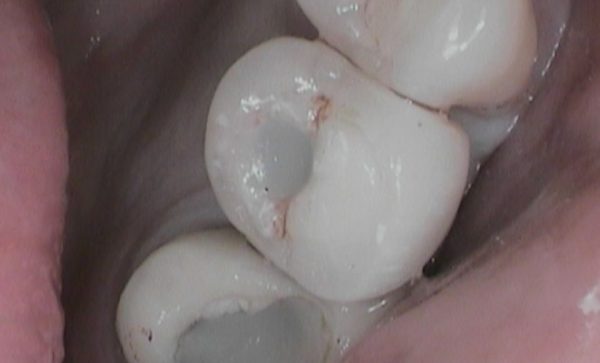

Before - Abacus Dental Before